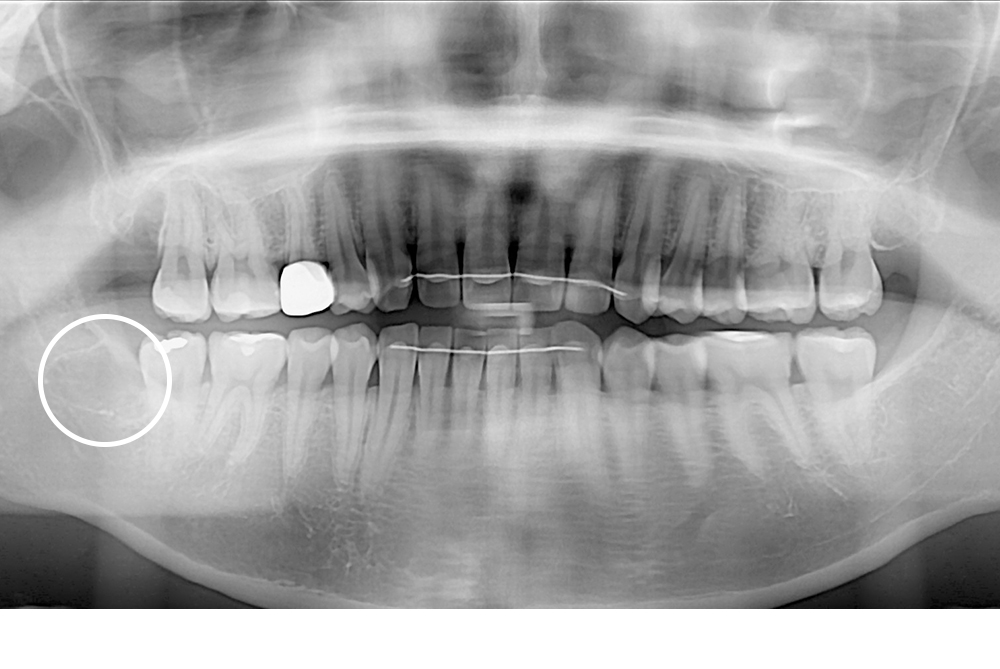

치료후 : 2018-01-17

세종치과는 구강악안면외과학 박사이신 원장님이 발치하는 치과입니다.